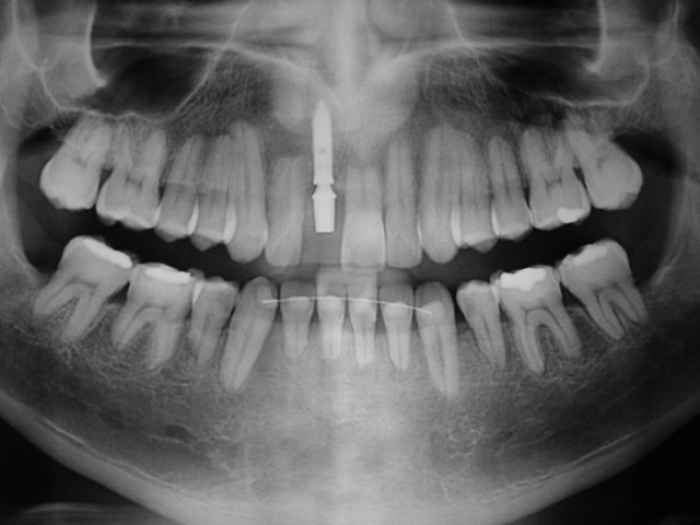

Rx com prótese fixa em porcelana

Raio X final